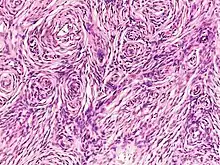

| Neurofibroma of the skin in a person with neurofibromatosis type I | |